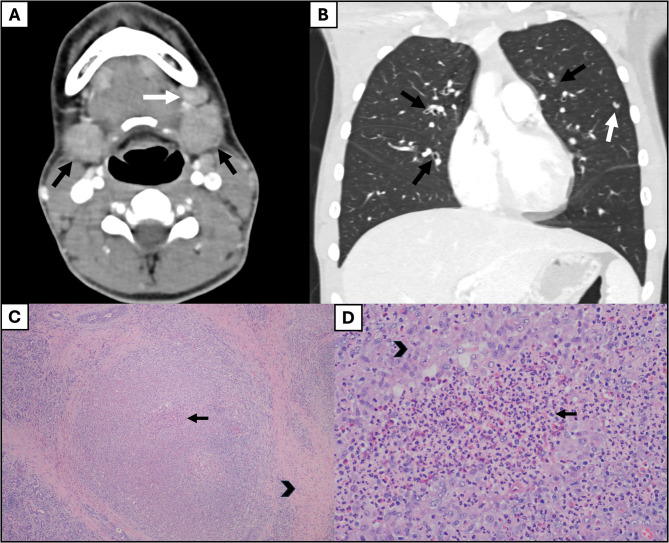

Case presentation: Case one is a 13-year-old male with asthma and allergies who presented with one month of cough and periorbital edema and subsequently developed submandibular swelling. Evaluation identified chronic sinusitis, weight loss, positive c-ANCA and anti-MPO IgG antibodies, peripheral blood eosinophilia, pulmonary eosinophilia, tracheal and pulmonary nodules, and eosinophilic infiltration of the submandibular salivary gland with granulomas and fibrosis fitting a diagnosis of EGPA. He improved with glucocorticoids and mepolizumab with a significant partial response, and eventually switched to benralizumab and mycophenolate mofetil with complete response. Case two presented at 19-months-old in acute respiratory distress with a history of reactive airway disease. EGPA diagnosis was confirmed on lung biopsy (eosinophilic capillaritis and interstitial expansion of eosinophils) in the setting of anti-MPO and p-ANCA positivity. He has done very well on mepolizumab for three years.